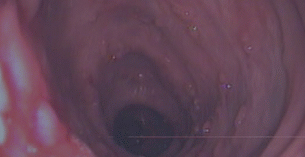

治疗直肠炎先做肠镜检查

早检查早治疗

To have a colonoscopy treatment of proctitis